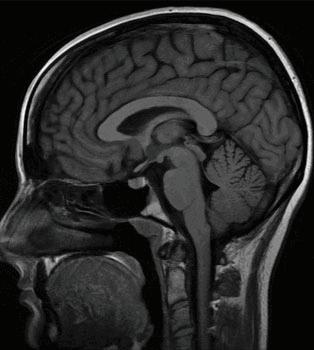

8 1 The Triune Brain Theory This is a model for the evolution of the vertebrate forebrain and behavior. The American physician and neuroscientist Paul D. MacLean proposed the theory that essentially three main parts of the brain control and regulate behavior as well as daily bodily functions, all of which are geared towards the body’s survival.

• The Brain Stem - The brain stem (or brainstem) regulates cardiac and respiratory functions for the body as well as the central nervous system. This central nervous system key to maintaining consciousness, regulation of sleep, heart rate, breathing, blinking, and eating (also known as circadian rhythms).

• The Cerebellum - The cerebellum is Latin for “little brain” that is responsible for coordination, balance, and gross motor control.

• The Cerebrum - The cerebrum is Latin for “brain” and it is the newest (evolutionarily) and largest part of the brain. It is where thought, decision-making, perception, judgment, and imagination occurs.

HTMBPR Figure 8.1 The Triune Brain (Cerebrum, Cerebellum, and The Brain Stem)